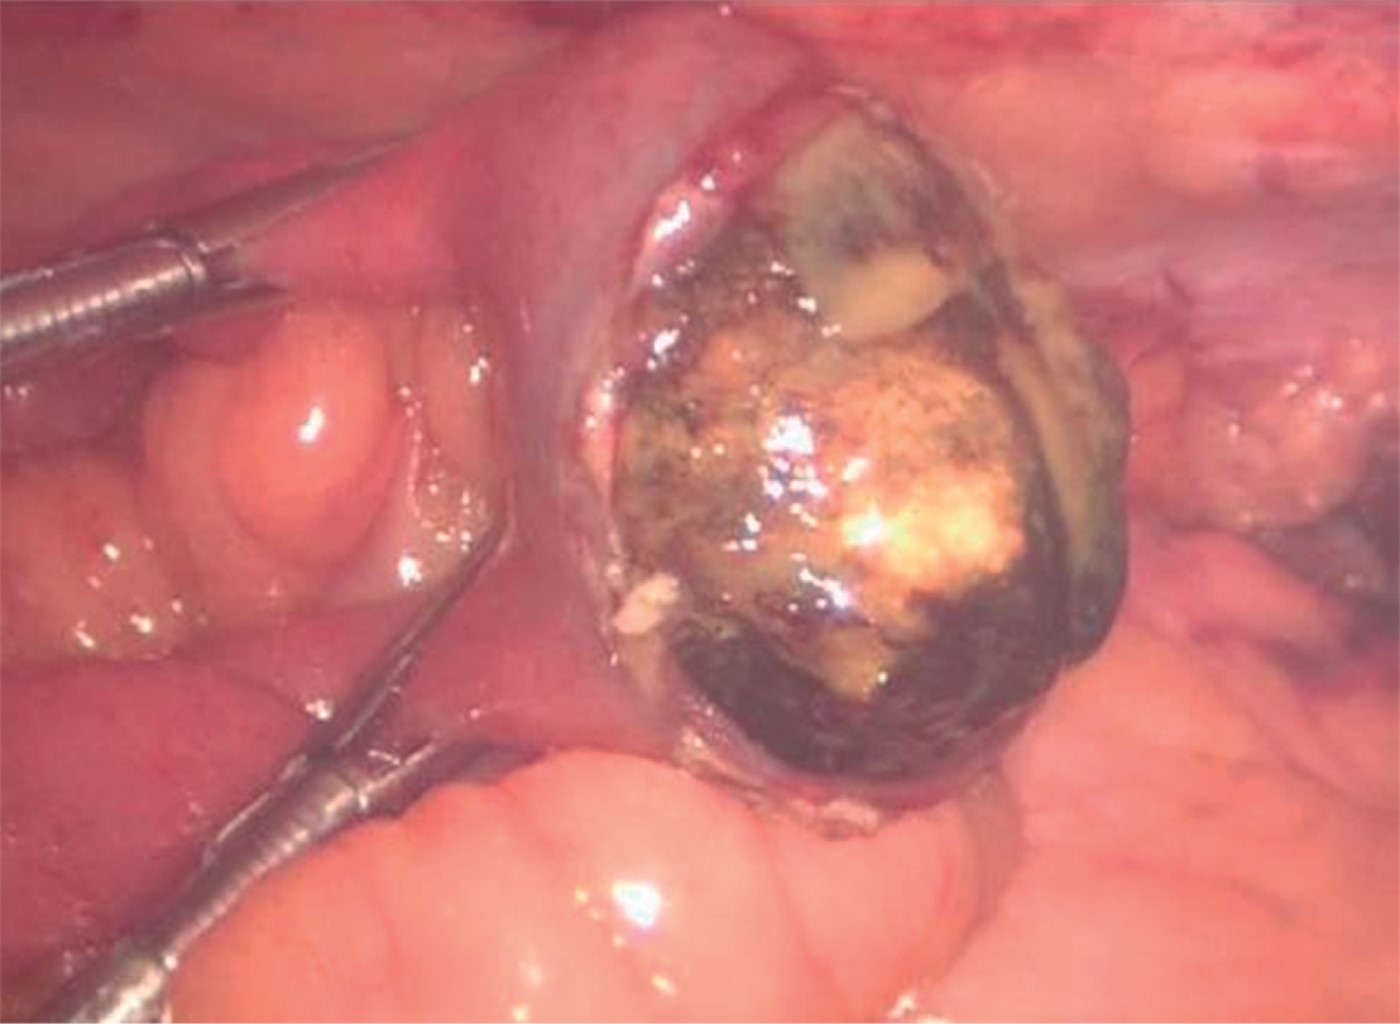

This is the case of a 59-year-old female patient with a history of a stroke event five years ago, type 2 diabetes under control with oral hypoglycemic agents (metformin 850 mg every 12 hours and glibenclamide 5 mg every 24 hours), hiatal hernia and ischemic heart disease under control. She also took acetylsalicylic acid 100 mg orally every 24 hours and atorvastatin 40 mg orally every 24 hours. Her condition began with nausea and vomiting of brown gastrointestinal contents, which leaded to intolerance to the oral route accompanied by pain in the epigastrium zone and referred in intensity of 7/10. She self-medicated with antispasmodics and nonsteroidal anti-inflammatory drugs (NSAIDs), with partial improvement; 48 hours after the onset of symptoms, the intensity of pain increased and she presented abdominal distension, as well as inability to pass gases through the rectum. On admission to the emergency department, the patient was found to be dehydrated, with distended abdomen, painful on superficial palpation and metallic noises on auscultation. A gastric tube was placed, and the aspirated liquid was fecaloid in appearance. Biochemically she had acute renal failure, hydro electrolyte imbalance and metabolic acidosis lab results. Radiographically, there were dilated small bowel loops, pneumobilia (Figure 1) and evidence of intestinal occlusion. In view of this, a laparoscopic surgical exploration was decided which showed dilatation of small bowel loops up to a segment of ileum, located 150 cm from the ileocecal valve, where a protrusion was observed that marked the end of the intestinal dilatation and that corresponded to a 3.5 cm interlocked biliary stone. An enterotomy with stone extraction were performed. The closure was in one plane, with continuous suture with 2-0 Prolene (Figure 2). During the intraoperative period, the patient had hemodynamic instability, so it was necessary to start support with norepinephrine (16 mg in 250 ml of 0.9% saline solution) at a rate of 8 ml/h, dose that was decreased until completely discontinued after 48 hours. Subsequently, she evolved favorably, being discharged on the fifth day while maintaining hemodynamic stability, tolerating the oral route and with no data of systemic inflammatory response. Currently, one year after surgery, she continues to be seen as an outpatient with no complications related to the surgical event.

Figure 2